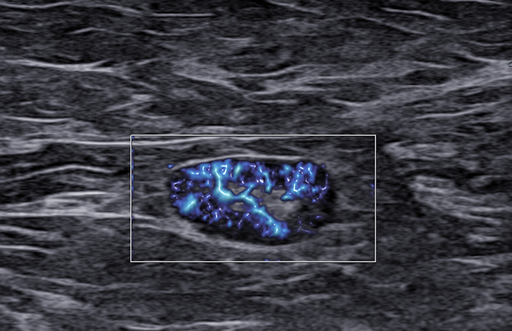

Ultrasonografia jest jedną z czterech głównych metod w diagnostyce chorób piersi. Obecna sytuacja epidemiologiczna, czyli ciągły wzrost zachorowań na raka piersi u kobiet, wymaga od nas dyskusji na ten temat. Od 20 lat zajmuję się problematyką diagnostyki gruczołu piersiowego. Dużo słucham, szkolę się, jak również przekazuję swoją wiedzę Państwu na licznych kursach, warsztatach, kongresach i sympozjach.

Zapraszam Państwa – wszystkich miłośników kobiecej piersi – do udziału w cyklu webinarów dotyczących głównie diagnostyki i leczenia chorób piersi. Będę się koncentrował na przekazywaniu Państwu praktycznej wiedzy oraz na tym, jak ją wykorzystać w ultrasonograficznej diagnostyce piersi.

Nagranie webinaru: BI-RADS-usg case story

Czy my rzeczywiście potrafimy czytać tę skalę? Dlaczego tyle jest rozbieżności?

Czy podział BIRADS 4 ma sens? Jak radzić sobie  z BIRADS 4a, b, c? Morfologiczne wskazówki